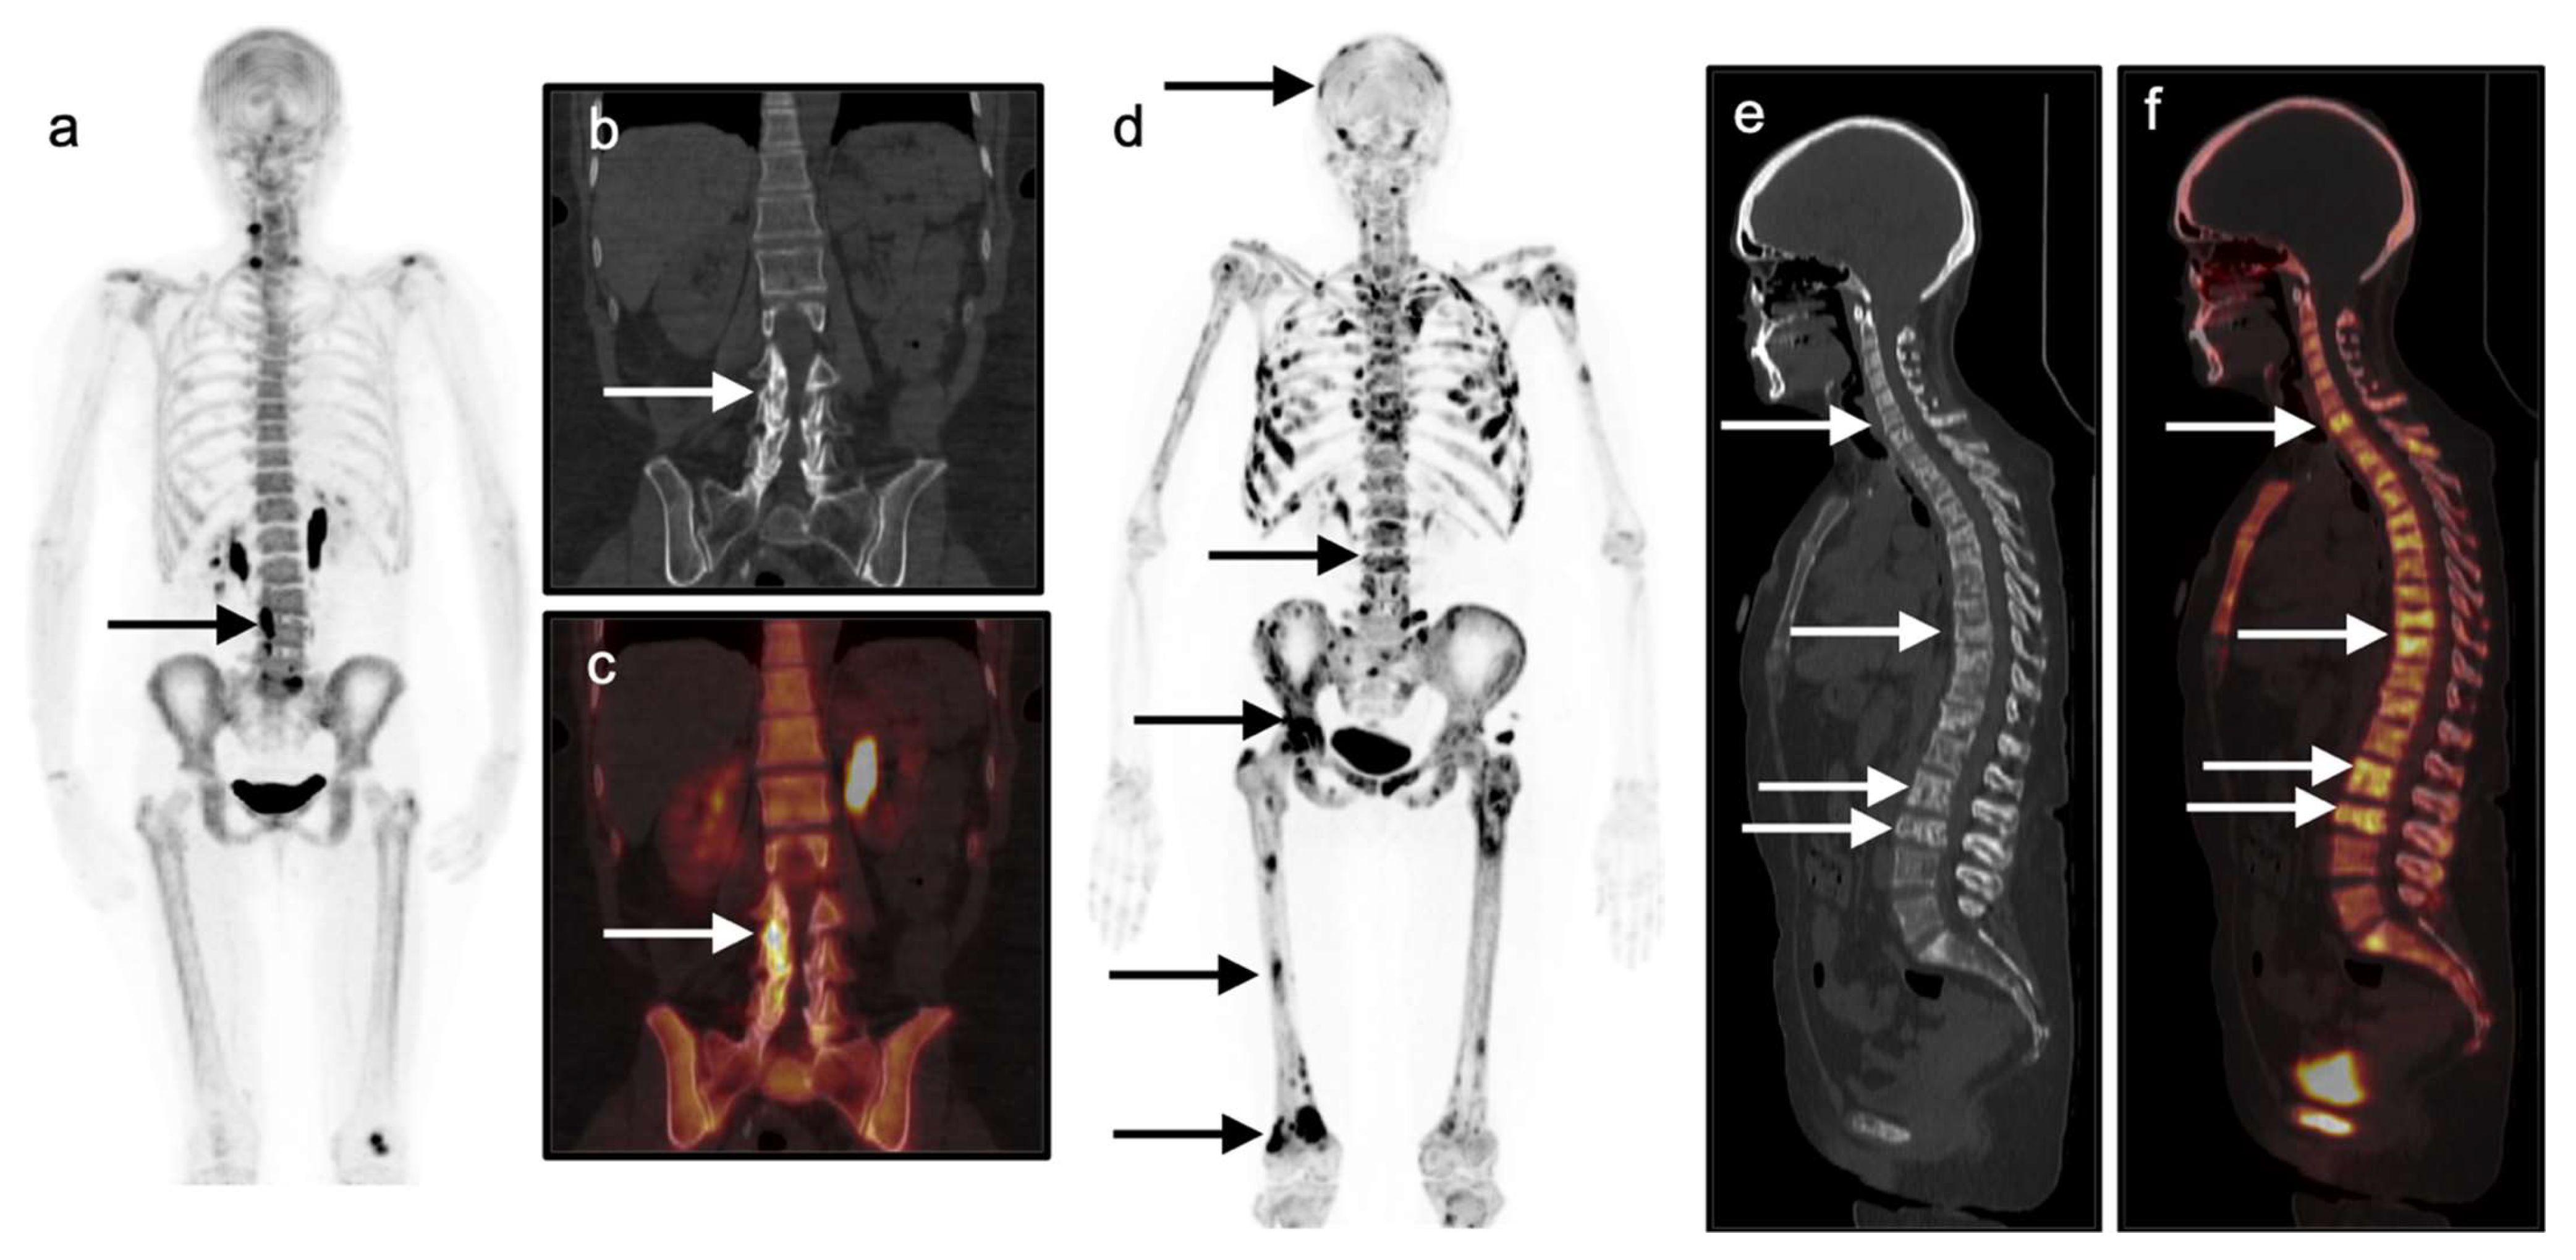

18F-NaF shows uptake that predominantly localizes diffusely throughout the bones and focally at sites of degenerative and/or post-traumatic change as well as sites of osseous metastatic disease (Figure 19). NaF PET-CT may occasionally show uptake in primary breast tumors irrespective of frank tumoral calcification, similar to that seen on 99mTc bisphosphate bone scans, but demonstrates an overall low sensitivity for detection of non-osseous sites of breast cancer [105]. Note that incidental focal abnormal FDG uptake in a breast lesion seen on an FDG PET-CT exams performed for indications other than breast cancer has a likelihood of malignancy that ranges from 27 to 55% [103,106,107].

Invasive lobular carcinoma (ILC) is a distinct molecular and pathologic entity from invasive ductal carcinoma and is the second most common type of breast cancer after invasive ductal carcinoma, comprising approximately 10–15% of invasive breast cancer cases in the United States [112,113,114,115,116]. Compared with IDC, ILC is more often difficult to identify on mammography, ultrasound, and FDG PET-CT [110,112,113,115,116]. ILC is also more often multifocal and bilateral compared with IDC [117]. Some ILC show hypermetabolic changes on FDG PET-CT as well as uptake on FES PET-CT (Figure 21). ILC may not take up FDG as readily as IDC for reasons that include lower tumor microvascularity, cellular density, proliferation rate, and number of glucose transporters [115,116,118,119,120,121,122,123]. ILC osseous metastases are more frequently present on FDG-PET-CT compared with IDC [118,119] as ILC osseous metastases are more frequently sclerotic, whereas FDG-PET-CT is more sensitive for lytic osseous metastases. Sclerotic ILC osseous metastases also may be indistinguishable from benign bone islands on CT at initial staging, thereby necessitating biopsy or imaging follow-up for confirmation of osseous metastatic disease [118,119]. Metastatic with of ILC may also occur at unusual sites, such as the stomach, uterus or colon [124].